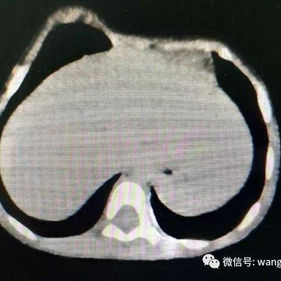

The patient is only 3 years old and had complex deformities of the anterior chest wall, featuring a protruding right side that appears ridge-like, while the central and left sides were flat and slightly depressed.

There are evident deformities on the anterior chest wall, with the right side protruding prominently and forming an acute angle deformity. The left side of the chest wall is relatively depressed, causing compression on the heart.